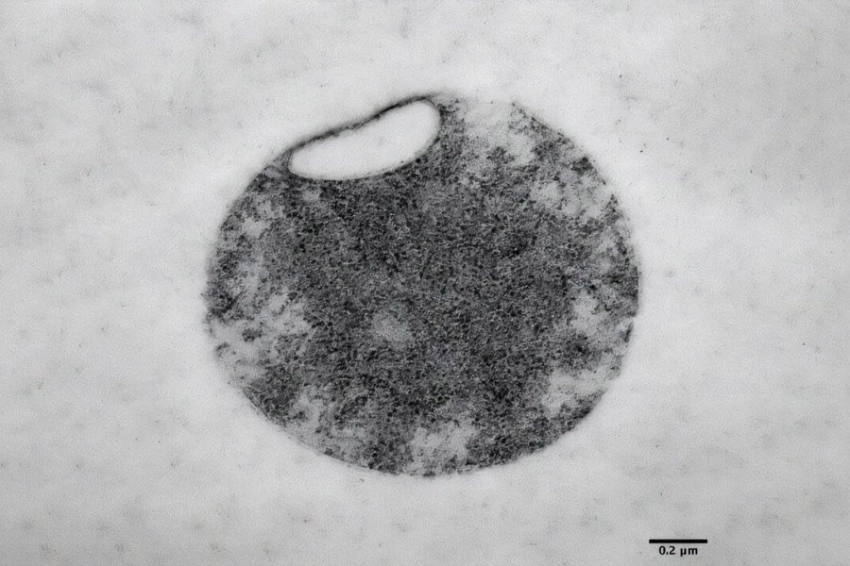

Результаты впечатляют: созданные кардиомиоциты демонстрируют четко сформированные саркомеры — «рабочие модули» мышечной ткани, а также высокую электрическую активность благодаря улучшенной работе ионных каналов. Особая структура клеток, включающая элементы клеточной мембраны (Т-трубочки), приближает их к настоящим сердечным клеткам.